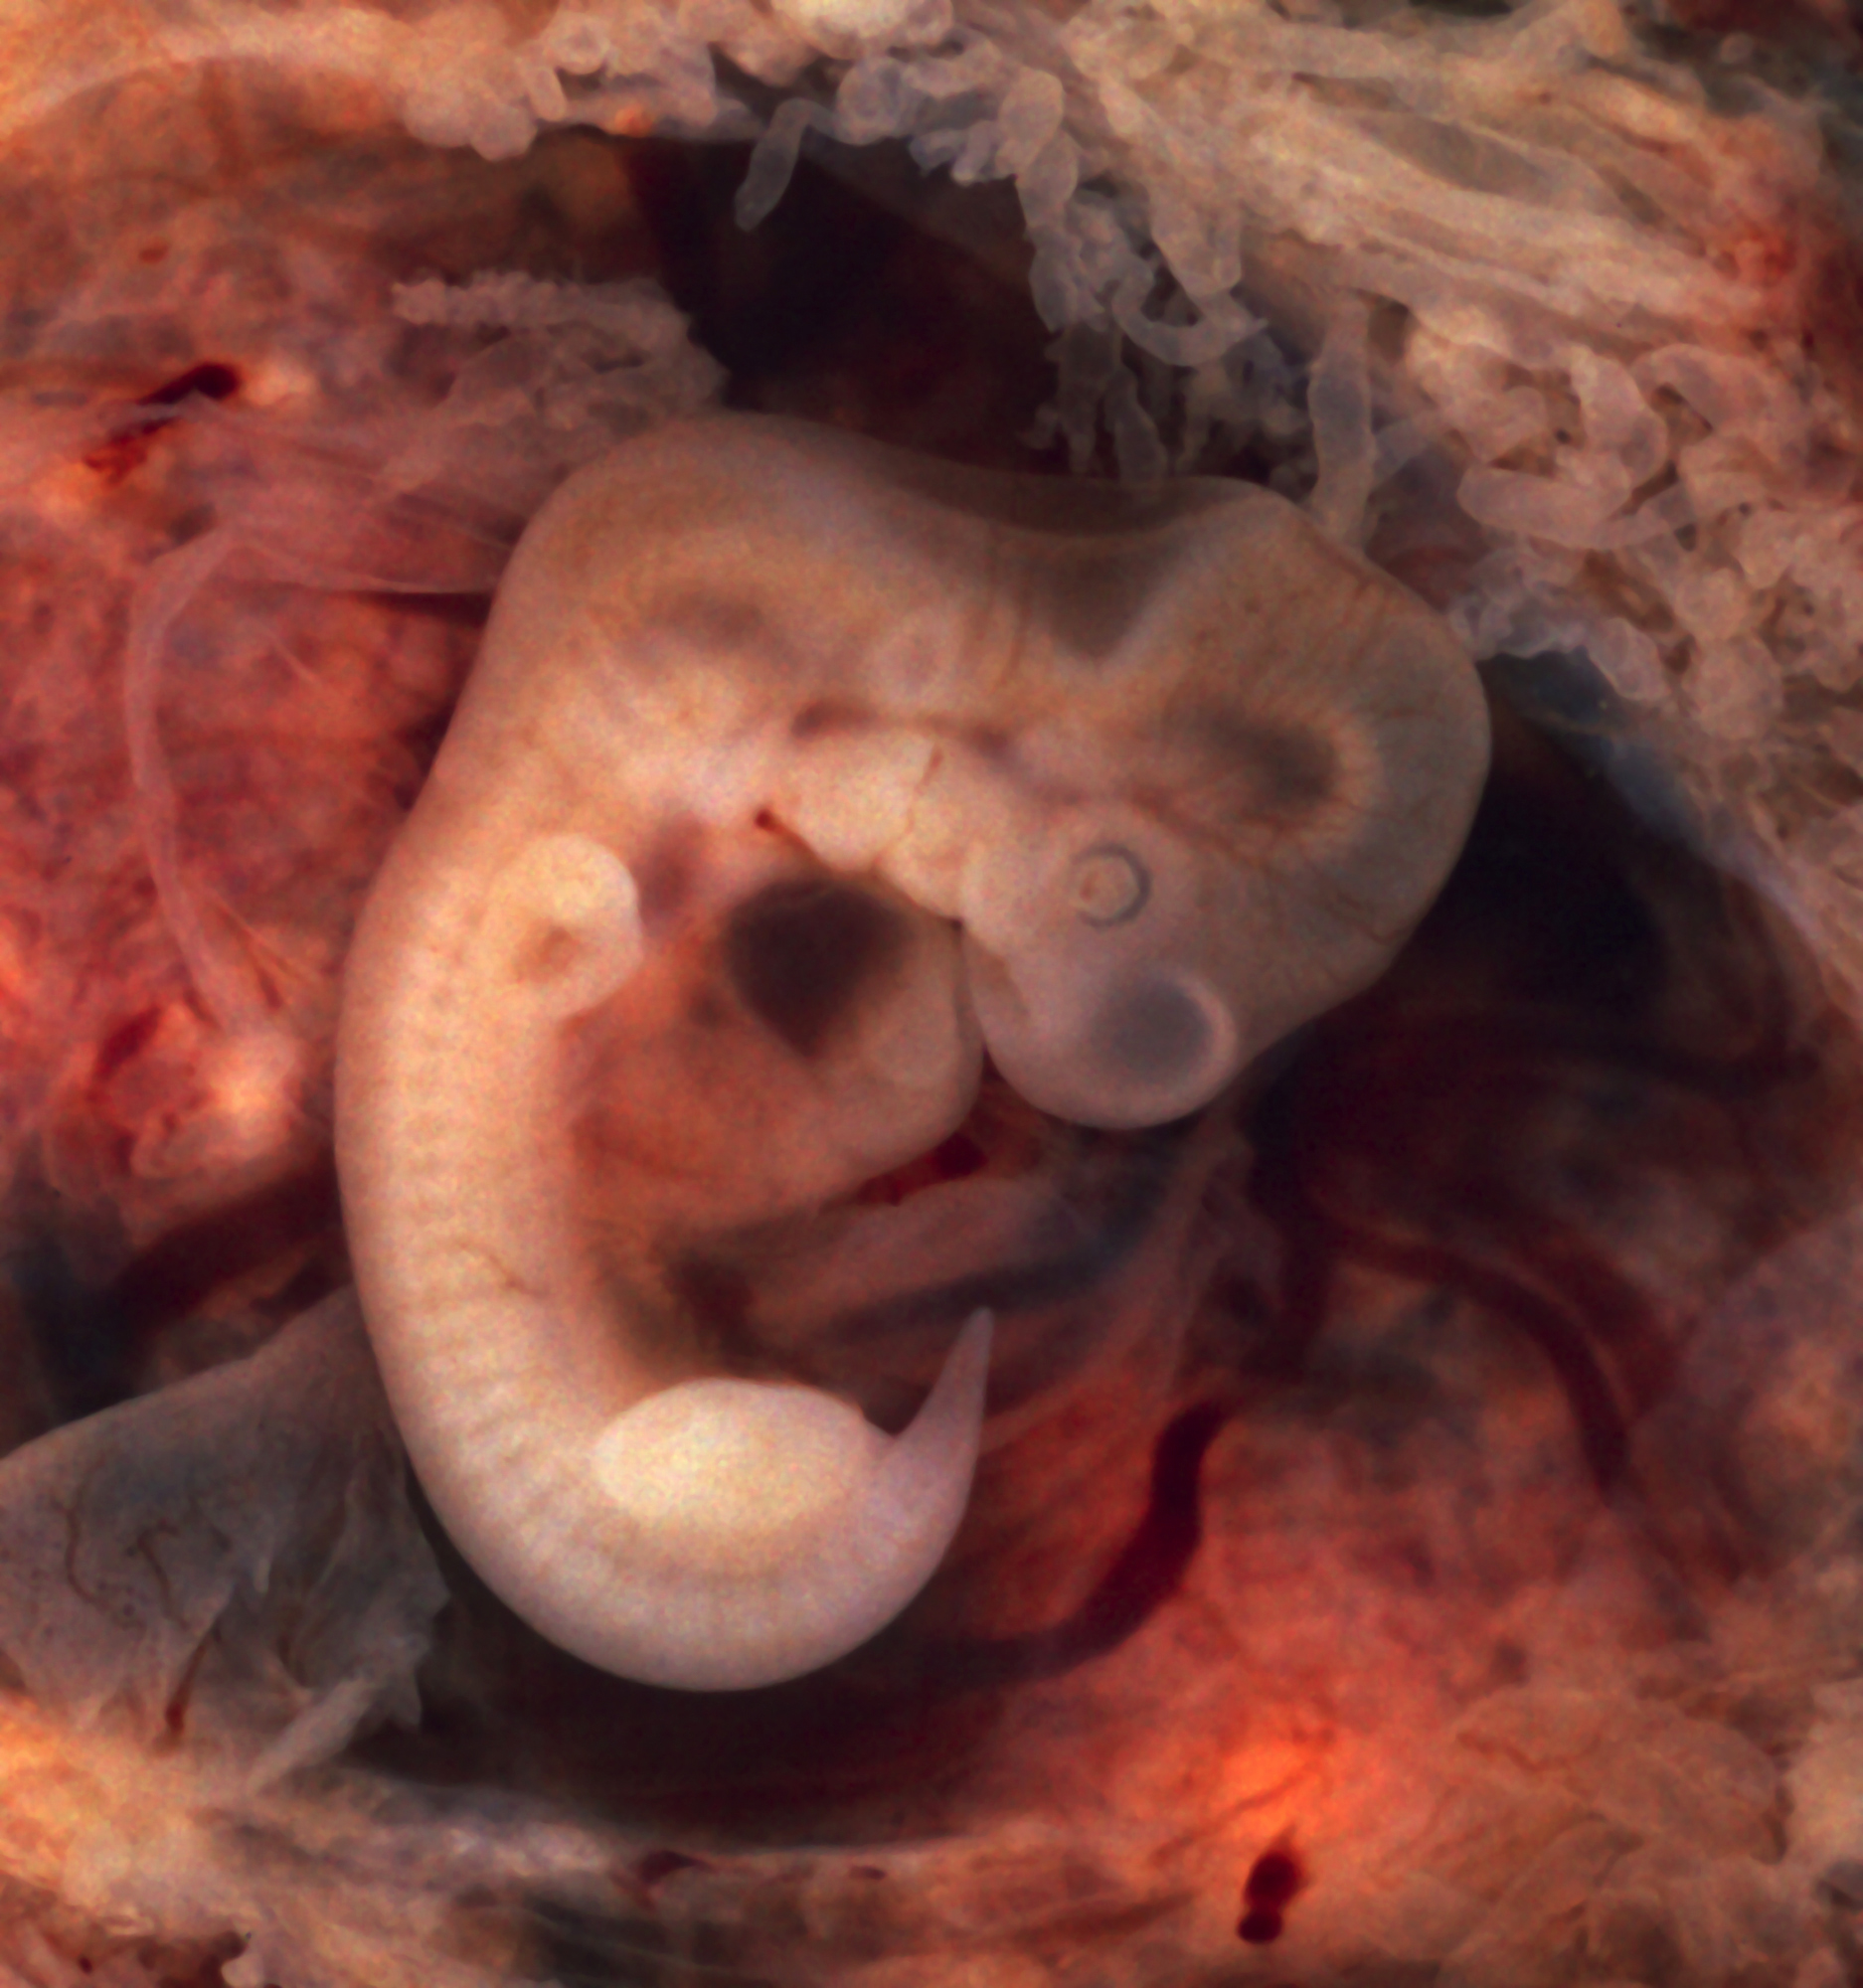

자궁외 임신의 대부분은 난관에 착상되는 경우이다. 임신은 난관의 여러 부위에서 발생할 수 있는데, 구체적으로는 난관 채 끝(전체 자궁외 임신의 5%), 팽대부(80%), 협부(12%), 난관의 각부 및 간질 부분(2%) 등이다.[35] 특히 협부나 난관의 간질 부분에 착상된 경우, 해당 부위의 혈관 분포가 많아 갑작스러운 대량 내부 출혈이 발생할 위험이 커 사망률이 더 높다.[35] 2010년에 발표된 한 검토에서는 난관 자궁외 임신이 손상된 배아-난관 수송으로 인해 배아가 난관 내에 잔류하게 되고, 동시에 초기 착상을 허용하는 난관 환경의 변화가 복합적으로 작용하여 발생하는 것으로 추정한다.[36]5. 2. 비난관 자궁외 임신